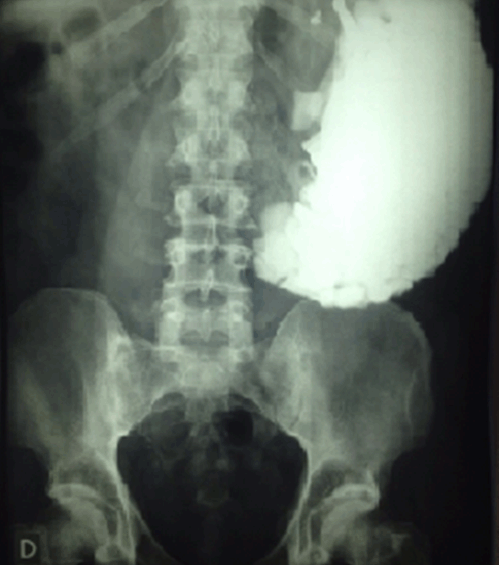

Plain abdominal radiograph showed no signs of intestinal obstruction and a dilated stomach with a giant radiopaque bezoar containing different-sized grouped smaller images. This finding was another important evidence for the diagnosis (Figure 1).

Figure 1: Abdominal radiograph with radiopaque gastric bezoars.

Radiographical diagnosis is especially valuable in litho bezoars, showing typically conglomerated radiopaque images within the organ. This unique appearance, "corn on the cob" sign, is considered pathognomonic. In this particular type of bezoar there is no need for barium studies or other image methods [4] [9] [10] .